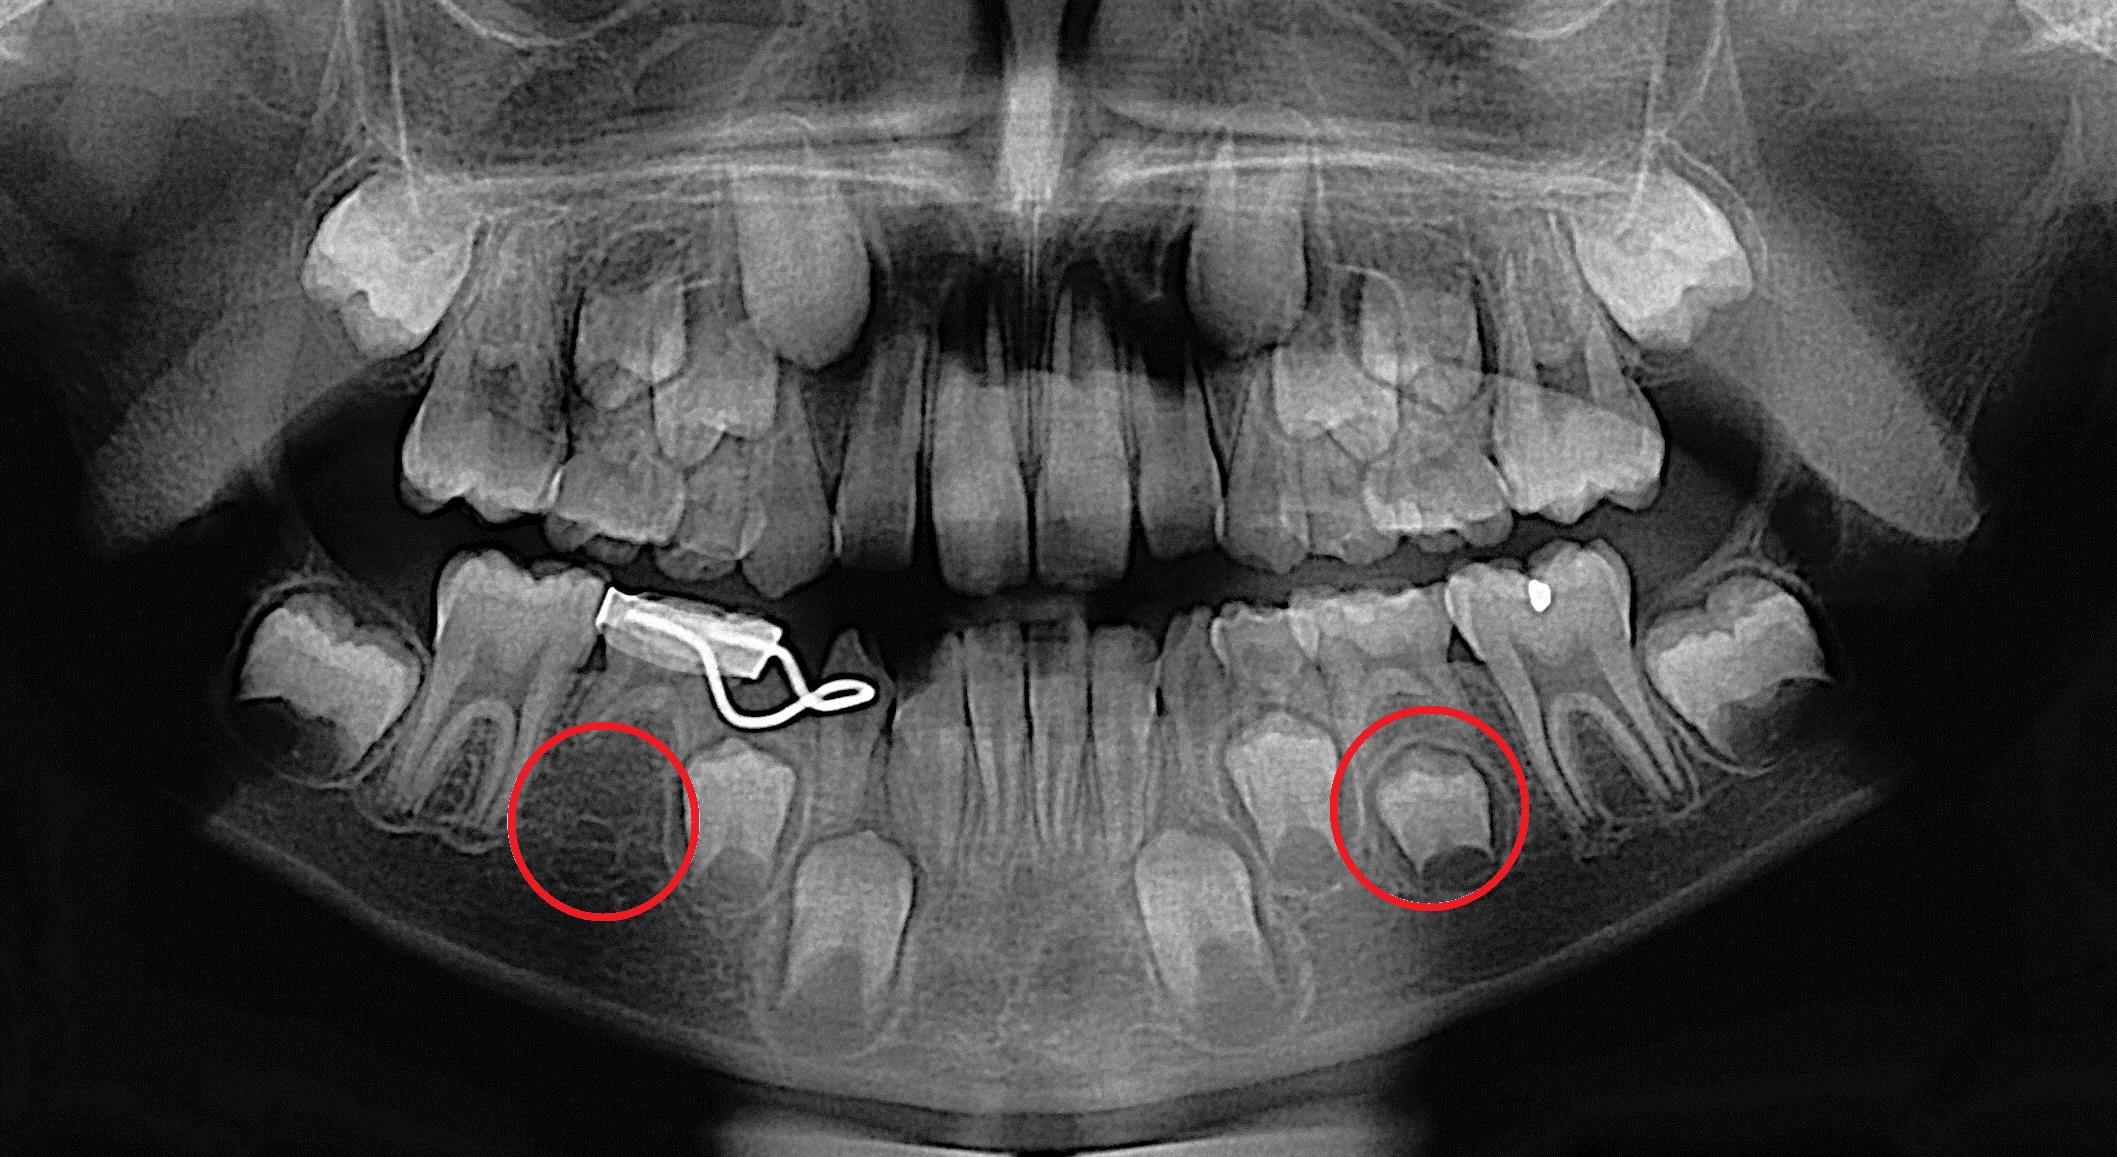

Symptoms of rotten teeth. MouthHealthy by the American Dental Association notes that children usually have 20 baby primary teeth that start coming in or erupting at about 6 months of age. It is not uncommon for adults to have baby teeth remaining and for people who have them as adults the second molar is usually retained.

Adult With Baby Teeth Causes Treatment And More

Baby Teeth In Adults Causes And Treatments Savina Dental Clinics

Adult With Baby Teeth Bonding Nundah Village Dental